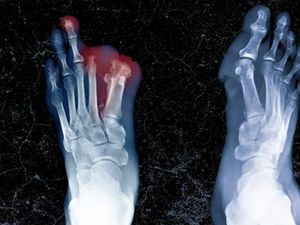

Pria ini terhindar dari tagihan nakal usai menunjukkan foto makanan yang dipesan. Ada pula kisah pemuda yang kakinya diamputasi karena makan makanan sisa teman.